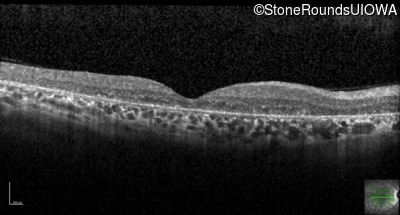

Optical Coherence Tomography - Left - 10/300 sc

Exemplar / OCT Stack

OCT Stack